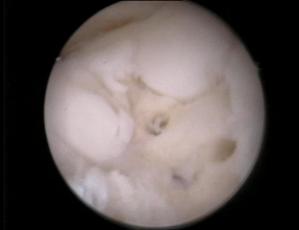

Examinarea artroscopica a genunchiului ramine standardul de aur in diagnosticarea si evaluarea leziunilor cartilajului articular. Examenul artroscopic permite evaluarea suprafetei cartilajului, a rezistentei la presiune, dar mai ales a marimii si profunzimii zonei leziunii condrale. Numeroase sisteme de clasificare a leziunilor cartilajului articular au la baza examinarea artroscopica directa a acestuia (vezi capitolul 2).

Examinarea artroscopica a cartilajului permite evaluarea mai multor caracteristici ale acestuia. Rezistenta cartilajului la presiune se efectueaza cu ajutorul exploratorului (probe), si se refera la forta cu care acesta este impins inapoi dupa ce presiune a incetat. Persistenta unei depresiuni condrale este semn de "inmuiere" a cartilajului. Artroscopic se evalueaza si culoarea cartilajului care normal este alba, lucioasa, cu usoara tenta galbuie. Cartilajul artrozic are o culoare galbuie marcata, este mat.

La examinarea artroscopica suprafata cartilajului este neteda, lucioasa, o fara discontinuitati. Pierderea luciului, prezenta unor depresiuni, fisuri, fibrilatii, delaminari sint semne de leziune. De asemenea, o zona de ingrosare a cartilajului, depresibila la examinarea cu exploratorul, este semnul unei leziuni profunde: "blister".

Modificari ale formei si conturului suprafetelor articulare in fracturi, osteocondrita, precum si prezenta de osteofite marginale in artroza (fig. 1.12) pot fi observate in cursul examinarii artroscopice a genunchiului.

Fig. 1.13. Imagini artroscopice - leziuni osteocondrale stadiu III B si C ICRS la nivelul condilului femural si la nivelul patelei |